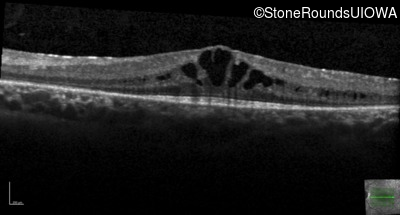

Optical Coherence Tomography - Right - 20/32

Exemplar / OCT Stack